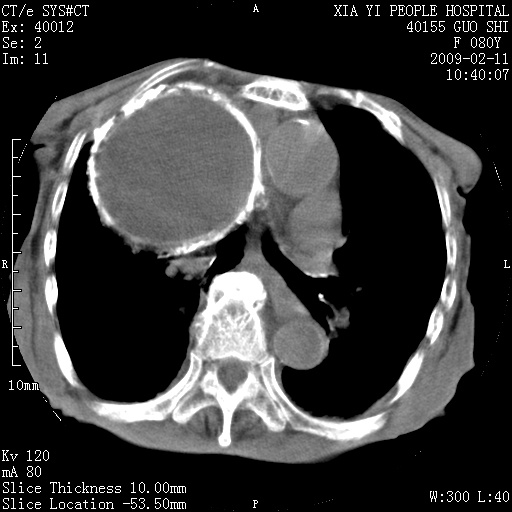

以下是引用随光逐影在2009-2-16 16:34:00的发言:[br]1)考虑右前纵隔皮样囊肿。2)双侧少量胸腔积液。

以下是引用zjzjr在2009-2-16 17:30:00的发言:[br]支持囊性畸胎瘤 双侧少量胸腔积液。